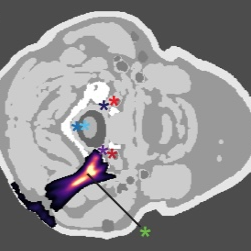

Target and Off-Target Locations

Facet joints from C2-3 to C6-7 were manually identified by a neuroradiologist on MR images. Off-target structures included spinal nerves, the spinal cord, and major arteries (vertebral, carotid).

Seg3D was used to segment MRI into 8 tissue types: water, CSF, vessels, fat, muscle, skin, bone, spinal cord. - Non-skin layers: thresholding → manual correction → isolation (Boolean Remove) - Skin layer: smoothed dilation/erosion on all-tissue mask + Boolean Remove

We used the Hybrid-Angular Spectrum (HAS) method to simulate ultrasound propagation. Transducers were modeled using the Rayleigh-Sommerfeld integral. Tissue acoustic properties were from the IT’IS Foundation database. Each model underwent 60 simulations (5 cervical levels, 2 sides, 3 angles, 2 transducers). Output was 3D pressure and power deposition. Nonlinear effects were ignored (P < 5 MPa).